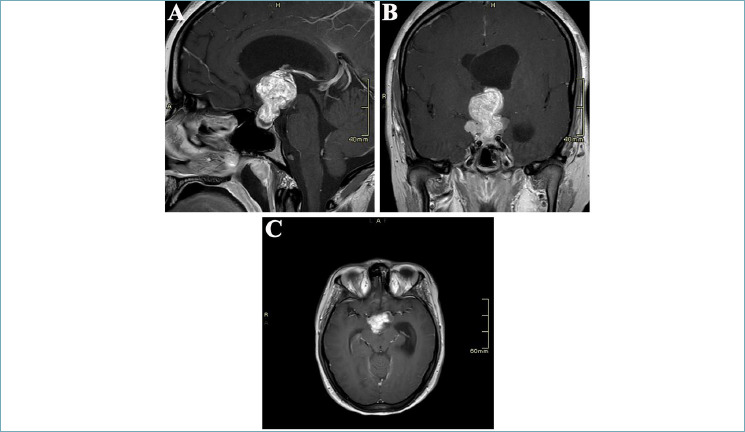

Embryonal tumors with multilayered rosettes (ETMR) are highly aggressive and therapy-resistant pediatric central nervous system (CNS) tumors that have three histological patters: embryonal tumor with abundant neuropil and true rosettes, ependymoblastoma, and medulloepithelioma. We present a case of ETMR in an 18-year-old woman with DICER1 syndrome. This report confirms the important role of DNA-methylation analysis in the classification of CNS embryonal tumors and the importance of investigating somatic and germline DICER1 mutations in all CNS embryonal tumors.

Abstract Image